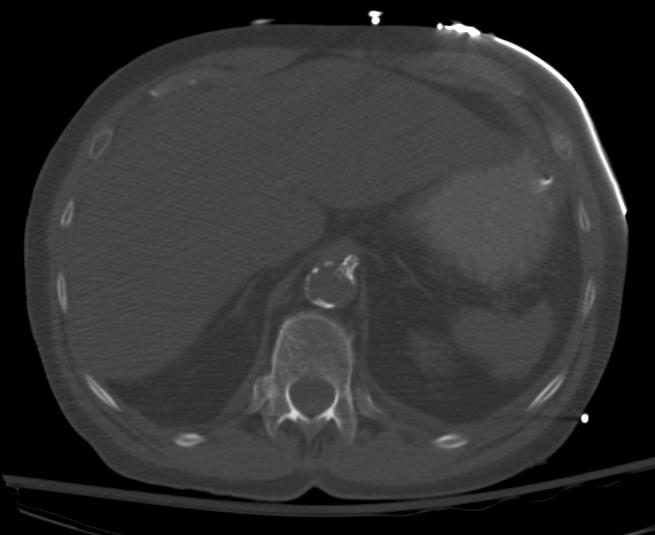

Mesenteric ischemia CT angiogram

Sagittal view of a CT angiogram demonstrating atherosclerosis at the ostium of the celiac artery and SMA

Celiac stent for mesenteric ischemia

Celiac artery stent as seen on axial image of CT